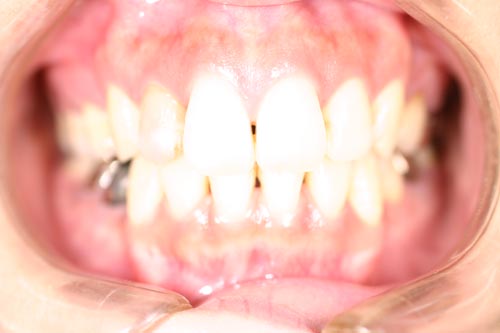

叢生の抜歯矯正の症例

Before

叢生ケースで4番の歯を4本抜歯し、唇側ブラケット矯正にて治療をした

年齢 30代

治療期間 2年6ヶ月

治療費用 1,000,000円

治療のリスク 特になし